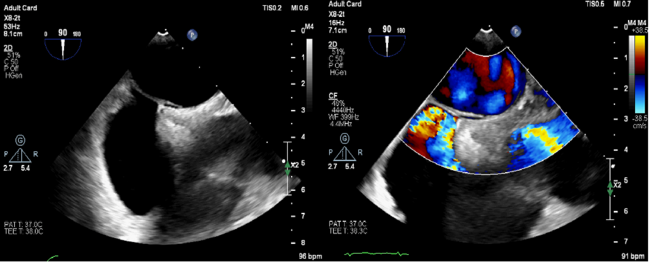

A 48-year-old man was admitted to our hospital with typical symptoms of TIA. Preoperative transesophageal echocardiography demonstrated PFO (Figure 1) and secondary septal pouch on the right (Figure 2, Video 1). Contrast transthoracic echocardiography (TEE) showed a moderate right-to-left shunt (Video 2). To close the secondary septal pouch and the PFO at the same time, successful atrial septal puncture was confirmed under the guidance of TEE (Figure 3A). Subsequently, a 25/25-mm Cera ASD occluder (LifeTech Scientific) was implanted (Figure 4). Post-implantation, the occluder was stable at the implant location (Figure 3B-D). Furthermore, the right-to-left shunt disappeared immediately (Video 3). Thus, ASD occluder implantation may be an effective simultaneous treatment of PFO and secondary septal pouch.

Figure 1. Preoperative TEE demonstrated the PFO. PFO right atrial opening and left atrial openings were 2.0 mm and 0.9 mm, respectively, and the length of the tunnel was 10.7 mm. TEE = transthoracic echocardiography; PFO = patent foramen ovale.